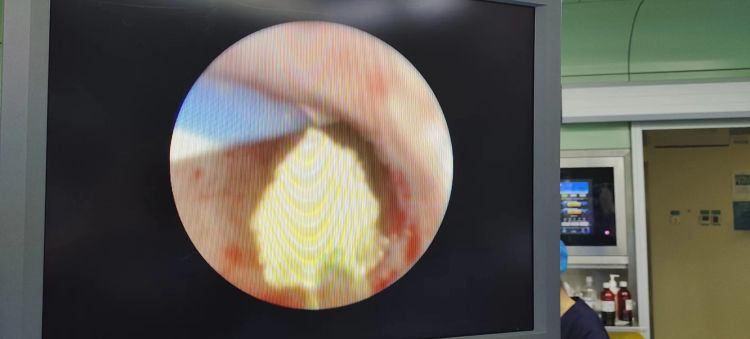

近日,漯河市骨科醫(yī)院(漯河醫(yī)專二附院)外二科收治一名13歲患者,腹痛多日,輾轉(zhuǎn)求醫(yī),經(jīng)泌尿外科王金柱副主任醫(yī)師會(huì)診后,確診為輸尿管中段結(jié)石,泌尿外科主任閆衛(wèi)甫和副主任醫(yī)師王金柱研究治療方案后馬上行微創(chuàng)手術(shù),術(shù)后恢復(fù)良好,這是我科治療最小年齡的結(jié)石患者,也是我院治療的最小年齡結(jié)石患者。

術(shù)中取石情況。

術(shù)中情況。